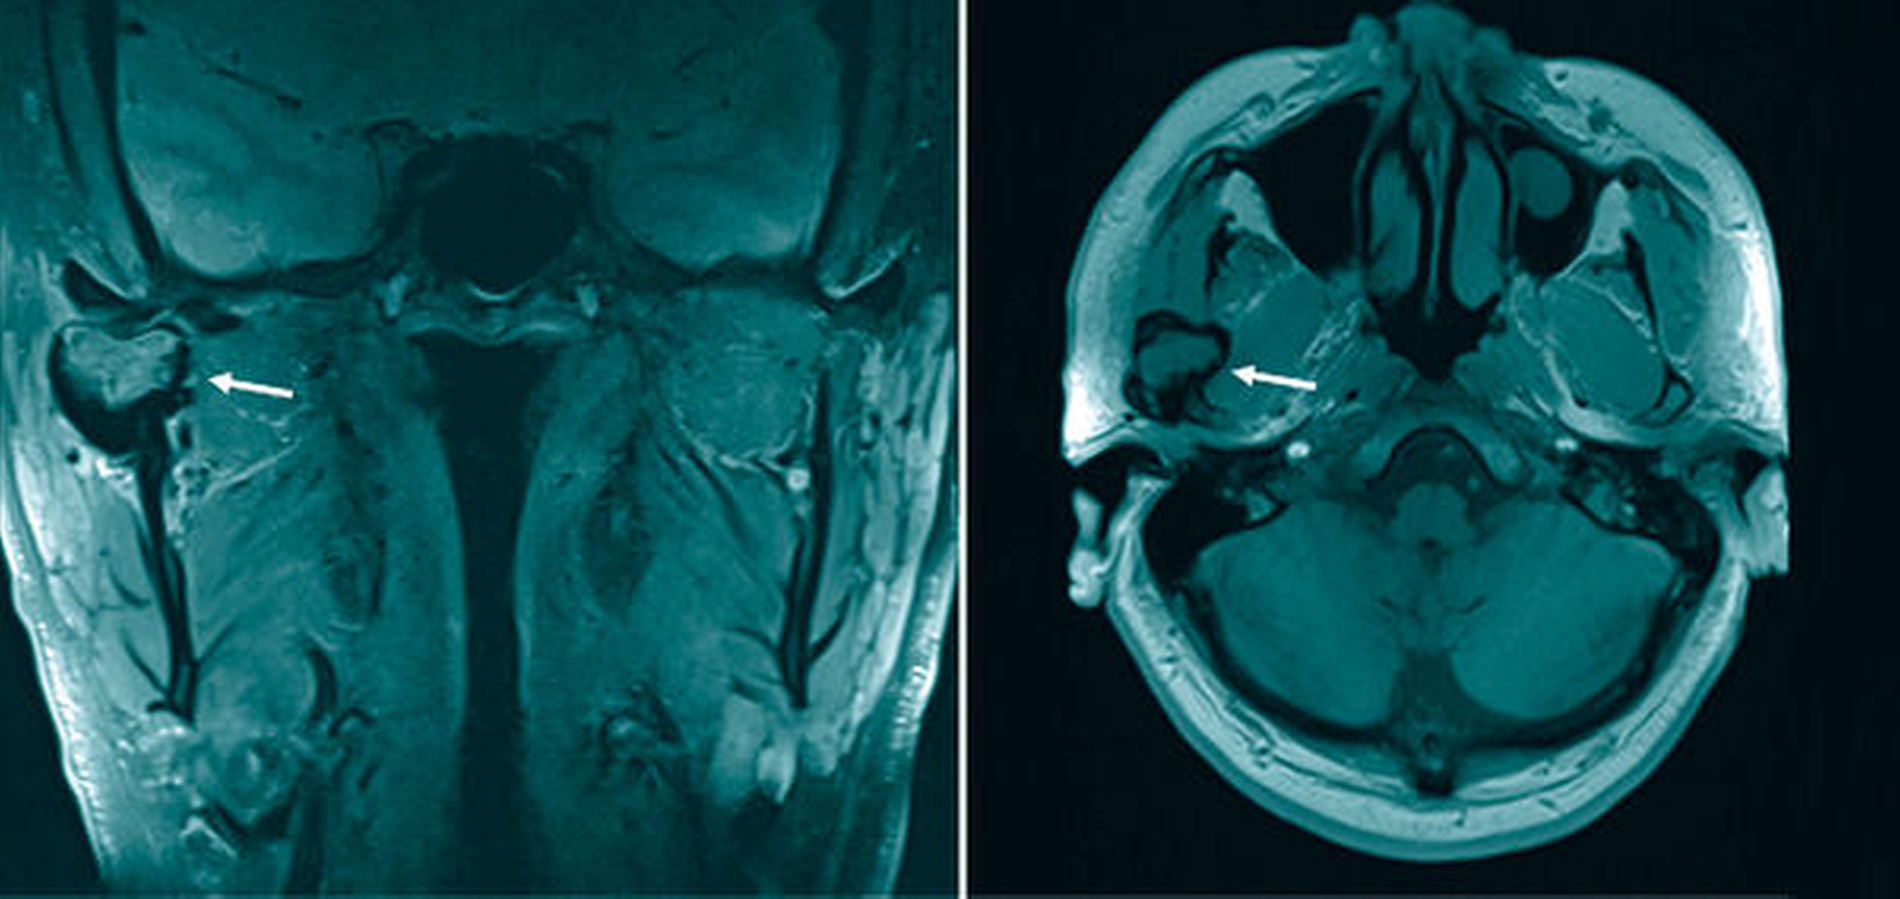

In der Panoramaschichtaufnahme (Abbildung 1) zeigte sich jedoch eine glatt begrenzte Aufhellung des rechten Capitulums. Zur weiteren Abklärung wurde eine Magnetresonanztomografie (MRT) des Gesichtsschädels veranlasst (Abbildung 2). Hier konnte eine Raumforderung im rechten Kiefergelenk nachgewiesen werden. Ergänzend wurde daraufhin eine CT-Untersuchung (Abbildung 3) durchgeführt, die einen im Durchmesser 31 mm großen Tumor mit Destruktion des rechten Capitulums zeigte.

Diese unspezifischen Symptome machen die Diagnose oft herausfordernd. Auch die zahnärztliche Bildgebung zeigt meist, wie in diesem Fall, nur unspezifische und keine wegweisenden Veränderungen. Die weiterführende Diagnostik sollte eine MRT und/oder CT umfassen. Hier zeigen sich häufig degenerative Veränderungen oder zystische Läsionen im angrenzenden Knochen, wobei aufgrund der Seltenheit der Erkrankung eine klassische bildmorphologische Charakteristik bisher nicht beschrieben wurde [Wang et al., 2019]. In der MRT, die als Goldstandard gilt, findet sich typischerweise sowohl in der T1- als auch in der T2-Wichtung eine niedrige Signalintensität. Folglich ist es radiologisch schwierig, einen TSRZT von anderen Riesenzelltumoren abzugrenzen, zumal manche Autoren den TSRZT als Tumorentität innerhalb eines Spektrums verschiedener Erkrankungen sehen [Wang et al., 2019].